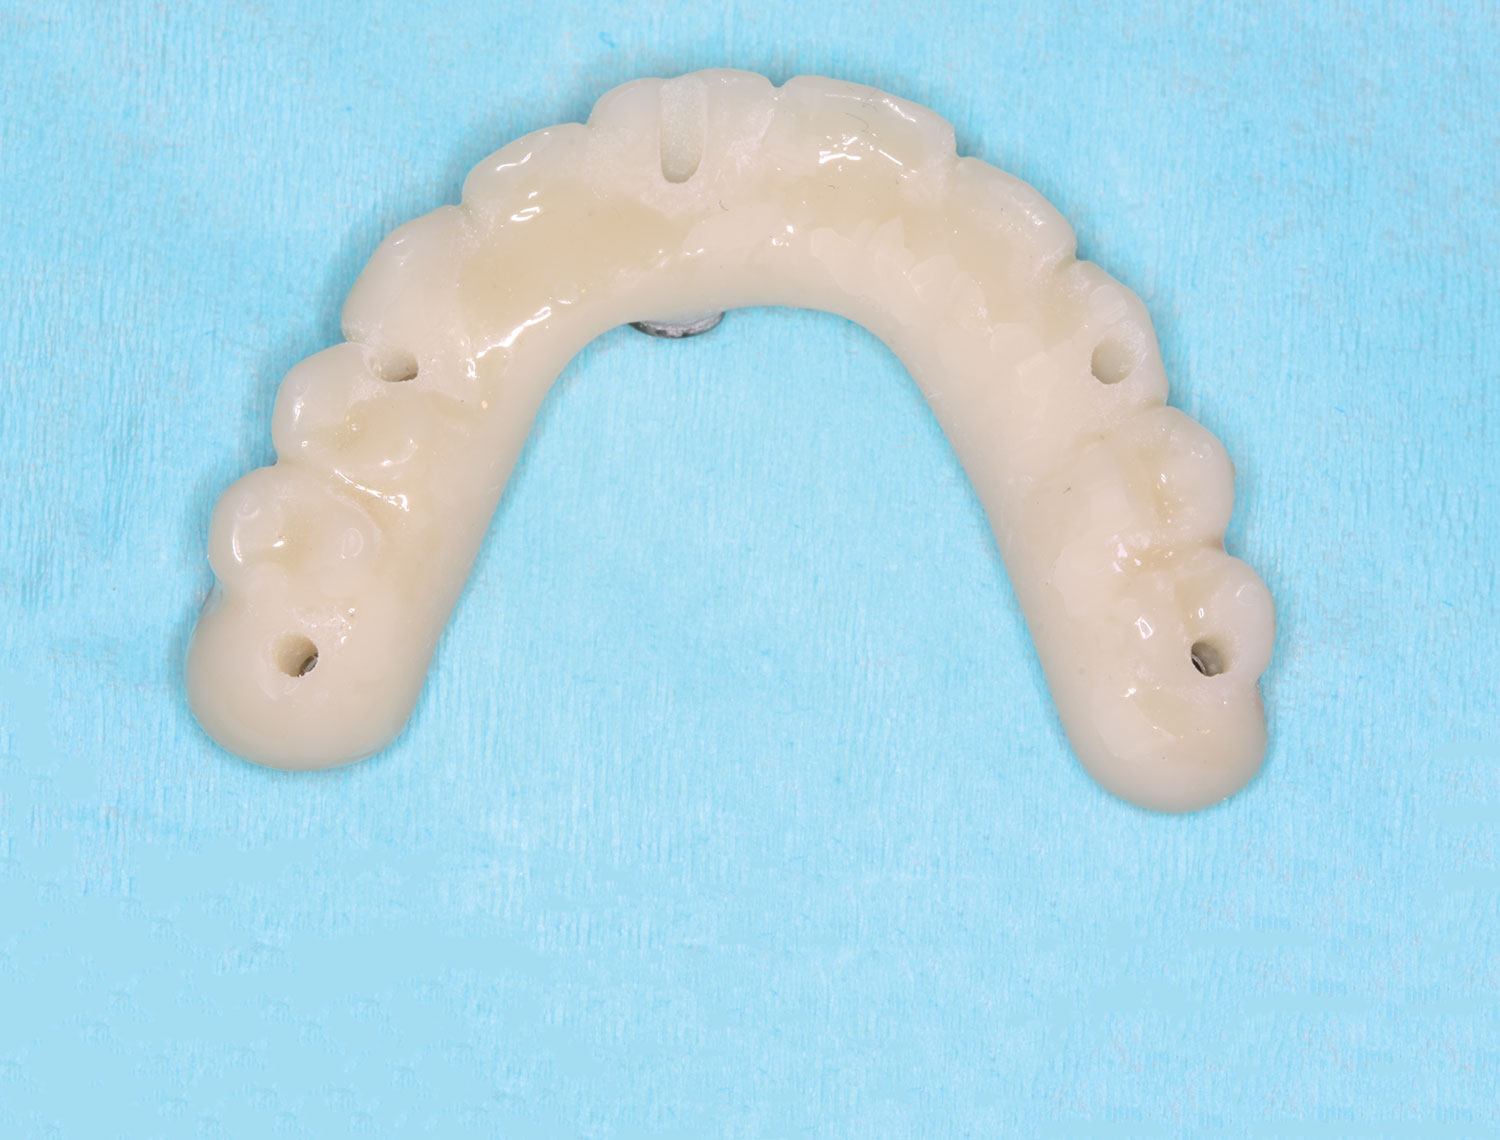

The implant company then returned an STL design file electronically via email. The office staff sent this file to the practice's 3D printer, and the appropriate color nanoceramic resin was used to print the prosthesis at 100 microns. Next, metal titanium (ti)-base cylinders, made specifically for the multi-unit abutments, were inserted into the prosthesis, which was then stained and glazed, and gingival color was applied to establish optimum esthetics (Figure 5).

Fig 5. Maxillary provisional prosthesis printed and ti-bases inserted.

Figure 5

Fig 16. Maxillary provisional prosthesis printed and ti-bases inserted.

Figure 16

Fig 17. Maxillary provisional prosthesis with screw-access holes in prosthetically correct locations.

Figure 17

Fig 31. Mandibular provisional prosthesis printed demonstrating screw-access holes in prosthetically correct positions.

Figure 31

Fig 37. Display of prosthetically correct screw-access channels in maxillary provisional prosthesis.

Figure 37

Figure 41